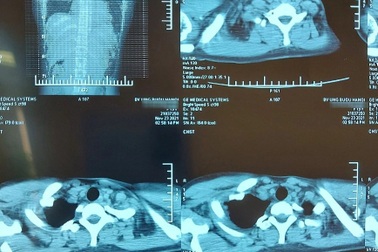

Cô gái trẻ bị u quái âm thầm "gặm nhấm" trung thấtĐi khám sức khỏe xin việc, nữ bệnh nhân 24 tuổi tình cờ được bác sĩ phát hiện có bất thường ở vùng trung thất. Khối u quái phát triển âm thầm, đe dọa tính mạng người bệnh.